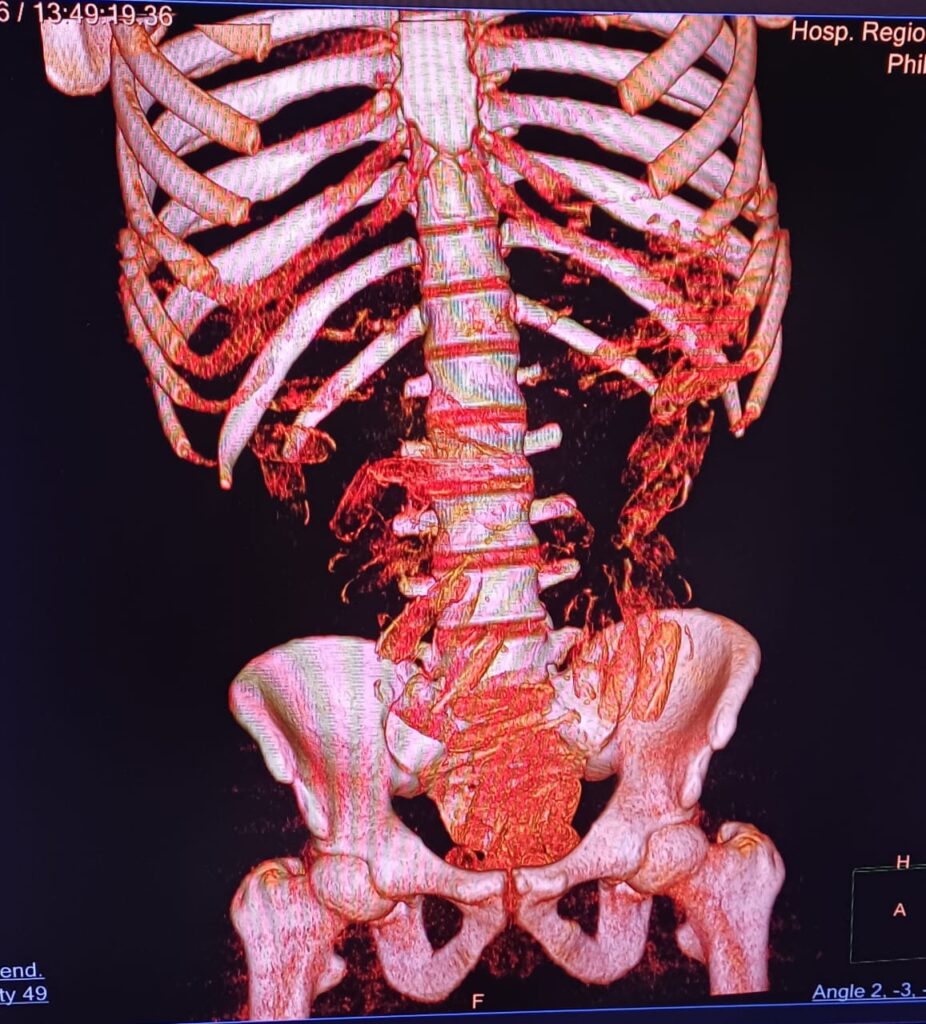

O trio era formado por dois homens e uma mulher. Em revista, os policiais encontraram cápsulas de pasta-base de cocaína. Foram levados para o Conjunto Hospitalar de Sorocaba e ali exames de imagem detectaram que os homens tinham drogas no estômago.